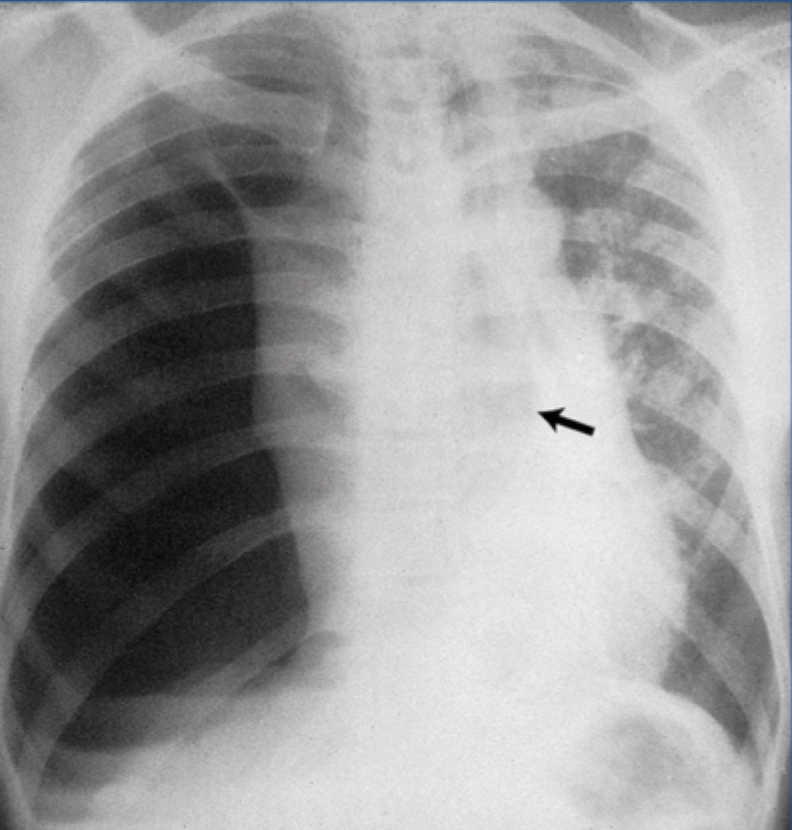

pneumothorax

what sign is this in pneumothorax

deep sulcus sign in supine pts